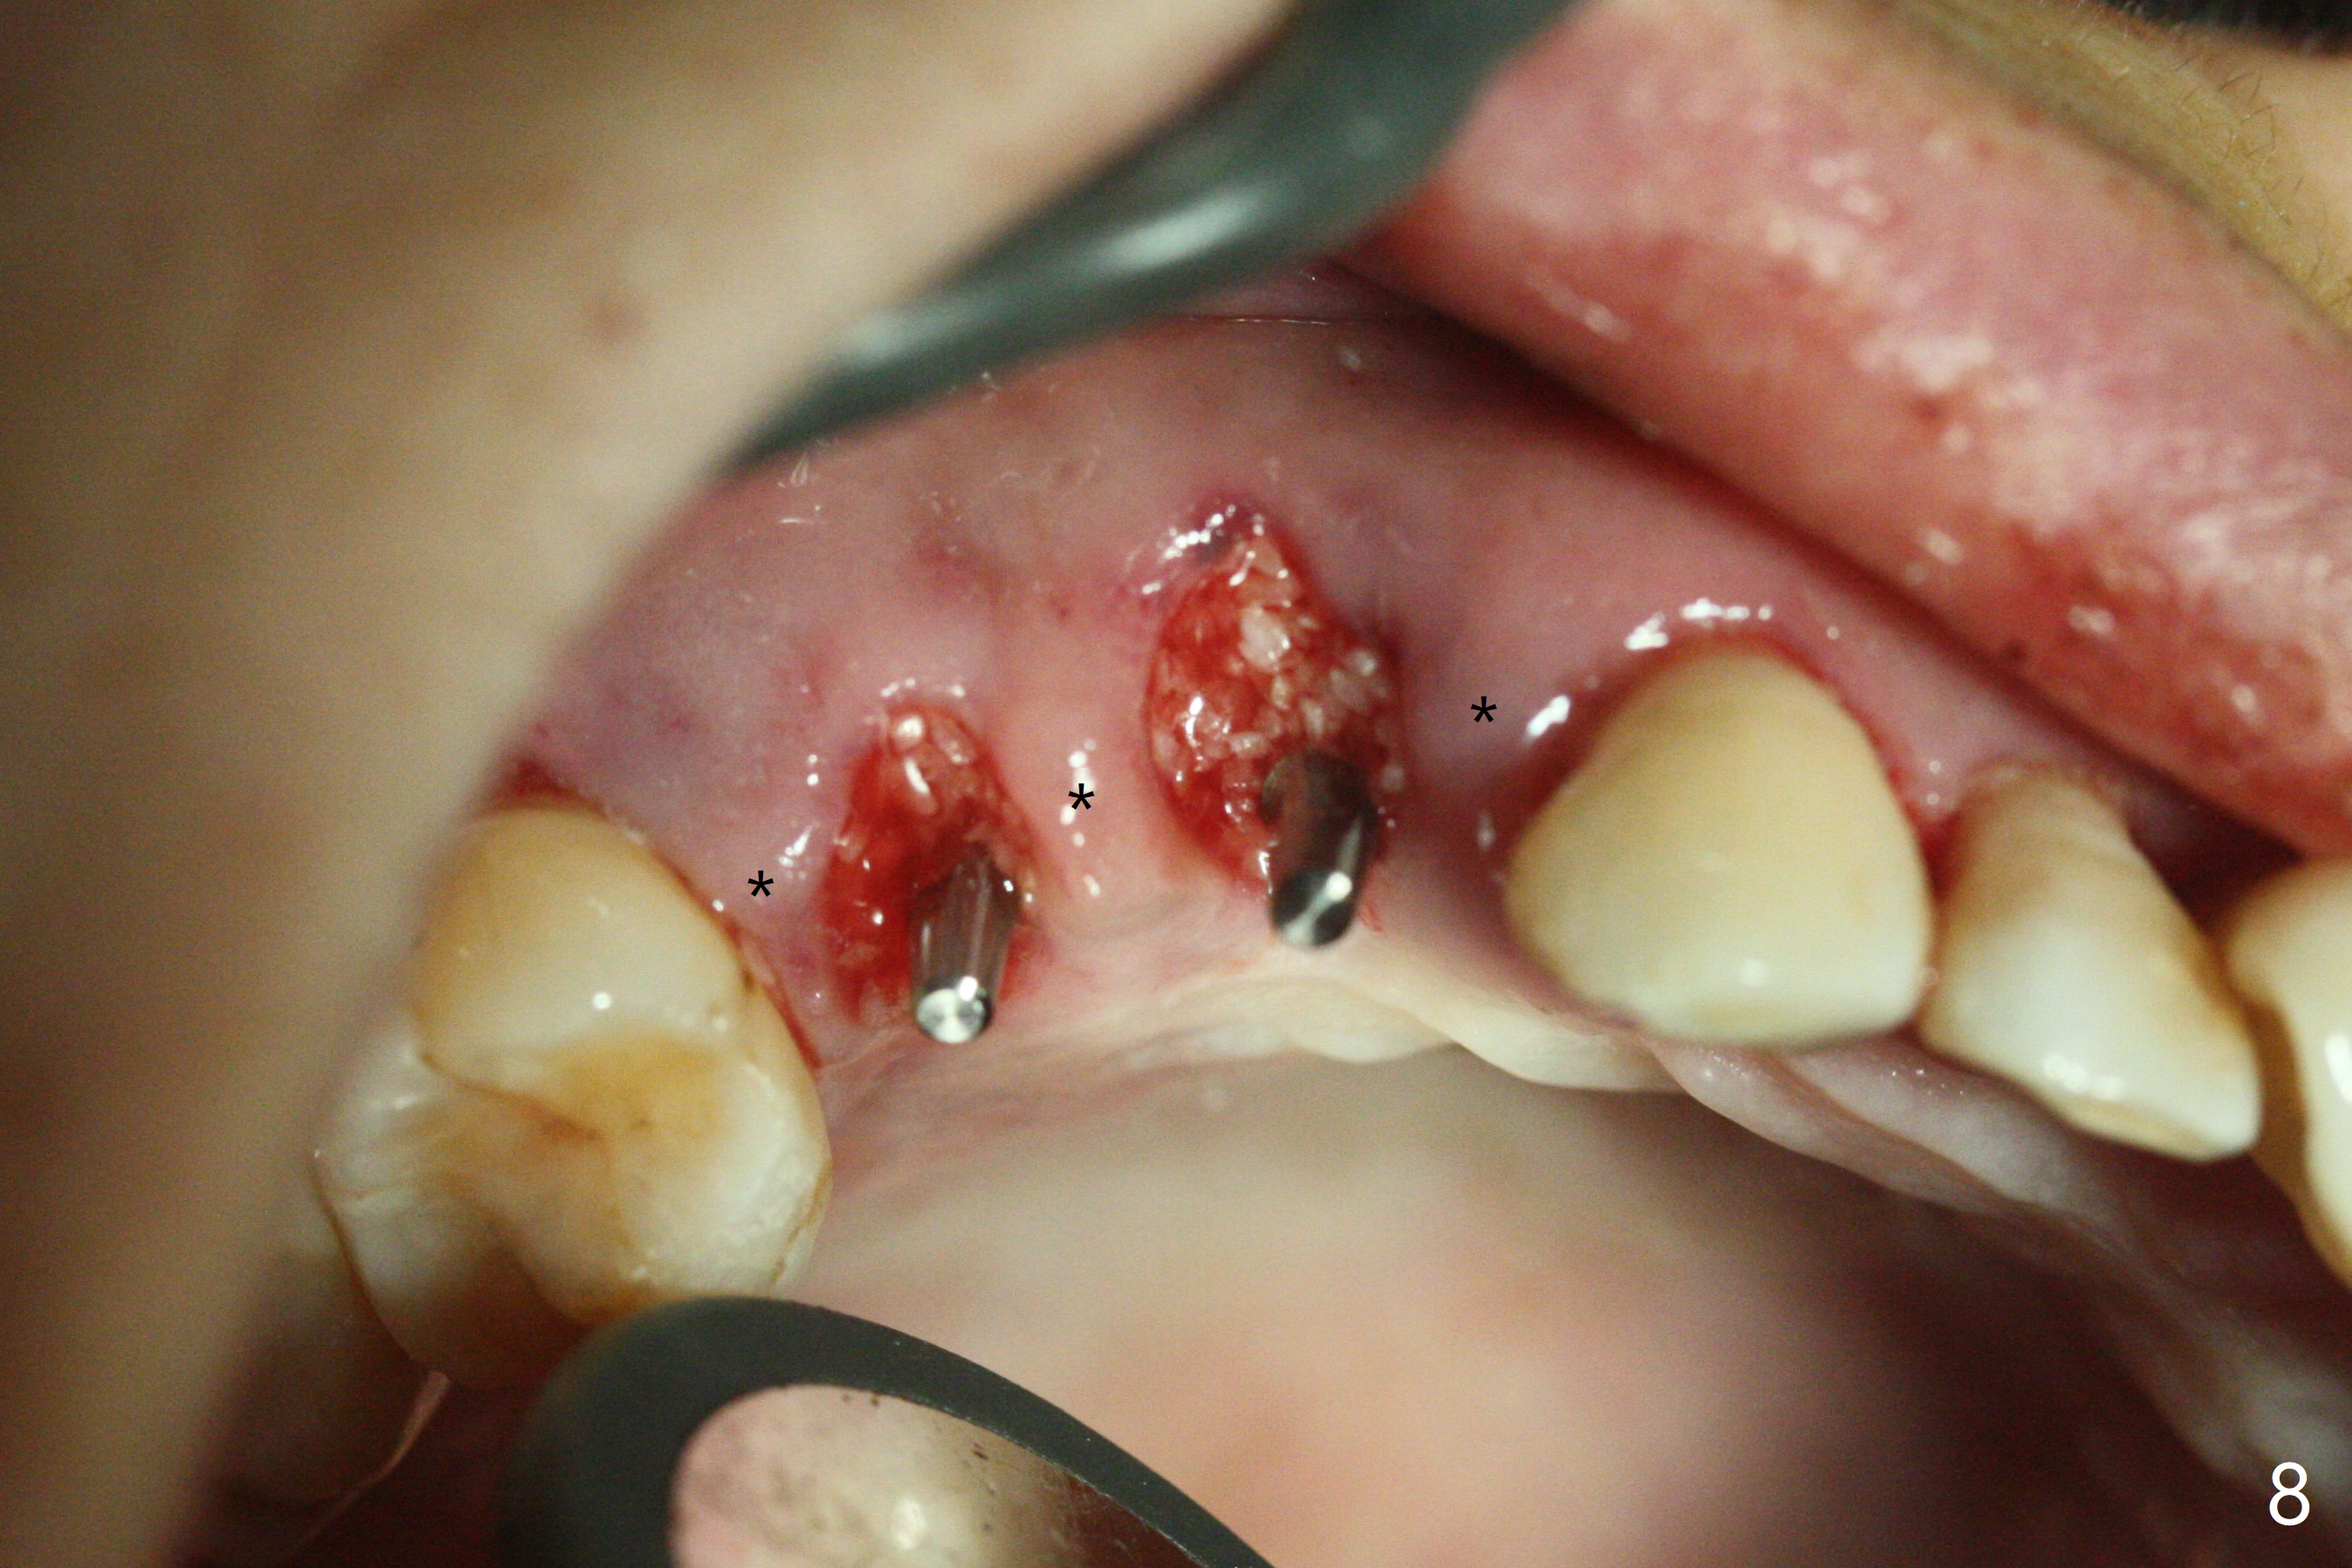

术前CT显示右上4牙槽骨比5窄(图一,二),3.5毫米植体比较合适,况且牙龈厚,基台长的一段式植体显得得当。为了取得最好的植体方位,4先拔除(图三),种植(图四),调整后者深度后,拔除5(术前征求病人同意),开始钻洞(图五),完成种植(图六)。粘性骨粉不仅放置于植体周围,而且6牙根近中(图七),4/5牙槽嵴和龈乳头(P)之间,减少术后龈乳头萎缩(图八:*)。制作两个分开临时牙冠,有利于维持龈乳头。对于病人来说,临时牙冠帮助咀嚼,而对侧拔牙创无法吃饭。术后3个月两个分开临时牙冠(其中一个龈方移位(图九:箭头)保持龈乳头(*)和牙龈外形(图十:*)。临时牙冠取出后,调整基台高度,少量钛屑(不妨大局)附着在健康的牙龈沟(图十一),再次显示两个基台之间龈乳头(图十二:*),衬里,修整的临时牙冠又插回牙龈沟(图十三:箭头),继续维持软组织形态,准备一个月后,调整基台边缘(图十二:箭头),取模。术后五个月大部分骨粉依然保留在植体和邻牙周围,龈乳头退缩不多(图十四: P)。三个月后(术后六个月)钛削无影无踪(图十五,与图十一对比))。永久性牙冠周围空间慢慢会消失(图十六,使用临时性胶水)。